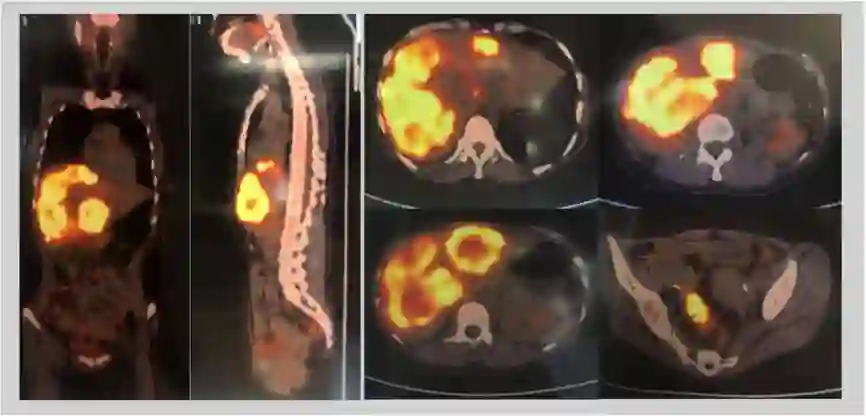

PET-CT提示:乙状结肠淋巴转移,肝内转移。

2017-10-30 PET-CT:1. 乙状结肠肠壁走形不均匀增厚、僵硬,FDG代谢异常增高,考虑恶性病变。周围肠系膜内多发稍增大淋巴结伴FDG代谢增高,考虑淋巴转移可能。2. 肝内见弥漫软组织块状影伴坏死,FDG代谢增高,考虑肝内转移。